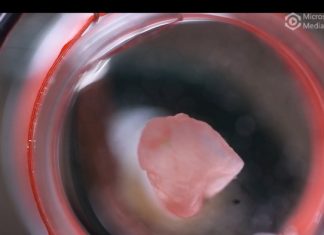

Study: A major step forward for organ biofabrication

Heart disease — the leading cause of death in the U.S. — is so deadly in part because the heart, unlike other organs, cannot...